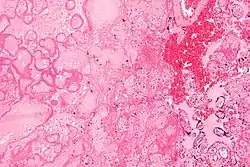

![]() صورة مجهرية لاحتشاء المشيمة، وهو السبب هنا لنقص الأكسجين في الرحم. صبغة الهيماتوكسيلين والإيوسين صورة مجهرية لاحتشاء المشيمة، وهو السبب هنا لنقص الأكسجين في الرحم. صبغة الهيماتوكسيلين والإيوسين | |